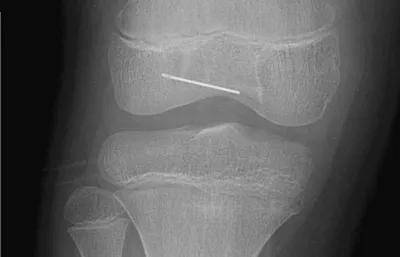

10岁·膝盖异物

半截针

患儿10天前不慎受伤,致半截床套针刺入右膝,无明显疼痛及活动障碍,至当地医院就诊摄片示右膝异物。